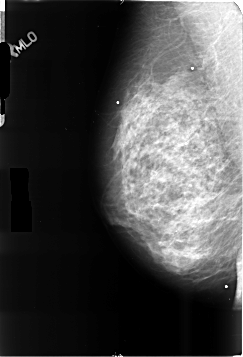

B_3500_1.LEFT_MLO

LEFT_MLO LINES 4696 PIXELS_PER_LINE 3104 BITS_PER_PIXEL 12 RESOLUTION 50 NON_OVERLAY